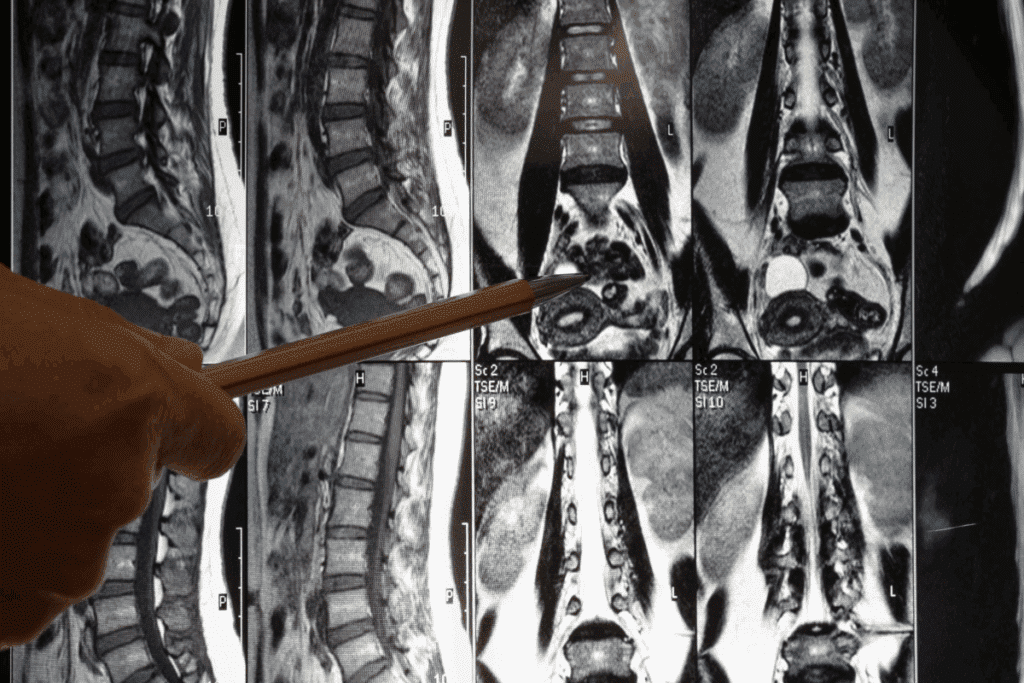

What Does a CT Scan of the Abdomen Show?

A CT scan of the abdomen is a powerful tool for doctors. It shows the organs, blood vessels, and bones in the belly area. This advanced imaging gives a detailed view of the belly, helping doctors find and treat many health issues.

Comprehensive View of Abdominal Structures

A CT scan of the abdomen gives a detailed cross-sectional view of the belly. It looks at the liver, spleen, pancreas, kidneys, and more. It can spot problems like tumors, cysts, or swelling in these organs.

Doctors use abdominal computerized tomography to check the size, shape, and position of belly organs. This is key for finding conditions that other tests might miss.

Detail Level and Resolution

CT scans of the abdomen show more detail than regular X-rays. They use X-rays and computer tech to make clear images. This means a high-resolution image of the belly’s tiny details.

When a CT abdomen with contrast is used, the details get even clearer. The contrast material lights up specific parts of the belly, making it easier to see problems.

Three-Dimensional Reconstruction Capabilities

Modern CT scans can make three-dimensional (3D) reconstructions of the belly. They do this by combining many cross-sectional images into one 3D picture.

The 3D reconstructions of a cat scan of abdomen help doctors see complex structures and how they relate. This is very helpful for planning surgeries and understanding how far a disease has spread.